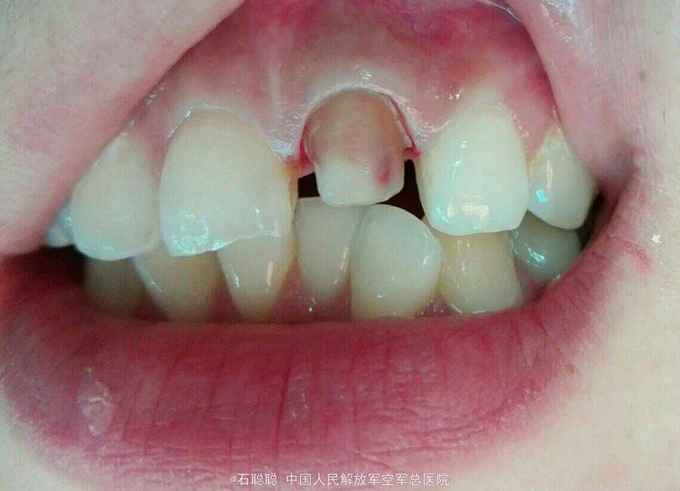

主诉:上前牙变色两年,要求改善牙齿颜色 现病史:诉两年前上前牙“变黑”,一年前该牙齿突发咬合不适,于外院行“根管治疗”,后无明显不适,自觉影响美观,来我科就诊 既往史:否认高血压、心脏病、糖尿病史,否认药物过敏史

诊断:21牙体缺损 12慢性根尖周炎 治疗计划:21全冠修复 12根管治疗后全冠修复 处置:21备牙,取模,比色A3,制作临时冠,调合,粘接 一周后复诊: 检查:21临时冠完整在位,无松动,叩痛-,牙龈未见异常 处置:21去除临时冠,试戴银钯合金烤瓷冠,调合、磨光,粘接

讨论:根管治疗后的牙齿由于血红素分解产物进入牙本质小管导致牙体变色,尝尝成为患者就诊的主诉,这个患者由于两个上颌中切牙存在切缘不均匀磨耗,形态不对称,颜色纠正效果较好,龈缘密合,患者很满意。嘱患者择期治疗12其36、46。